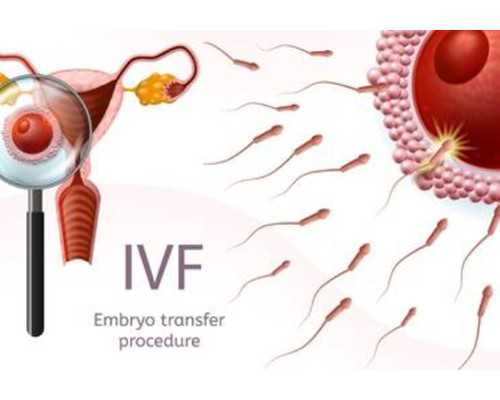

煙臺山醫院的試管嬰兒費用通常在3-8萬元之間。具體包括術前檢查、促排卵、胚胎培養及移植等環節。例如,術前檢查費用約為4500-9000元,促排卵藥物費用約為1-2萬元,手術及胚胎移植費用約為1-2萬元,總費用可能達到3萬元左右。但現如今煙臺山醫院試管可報銷,其自費的開銷變少。即,煙臺山醫院提供的試管嬰兒輔助生殖技術的醫保報銷比例大約為50%。報銷時,患者準備相關的門診病歷、輔助檢查單、門診慢病認定申請單以及夫婦雙方的身份證和結婚證等材料,到窗口報銷即可。

4、冷凍胚胎二次移植費用低

有無冷凍胚胎。假如夫妻做完一次移植后還有多余胚胎,能夠冷藏備用,要求交納胚胎冷凍保管費。假如要進行凍胚移植還需交納冷凍胚胎的復蘇費用。